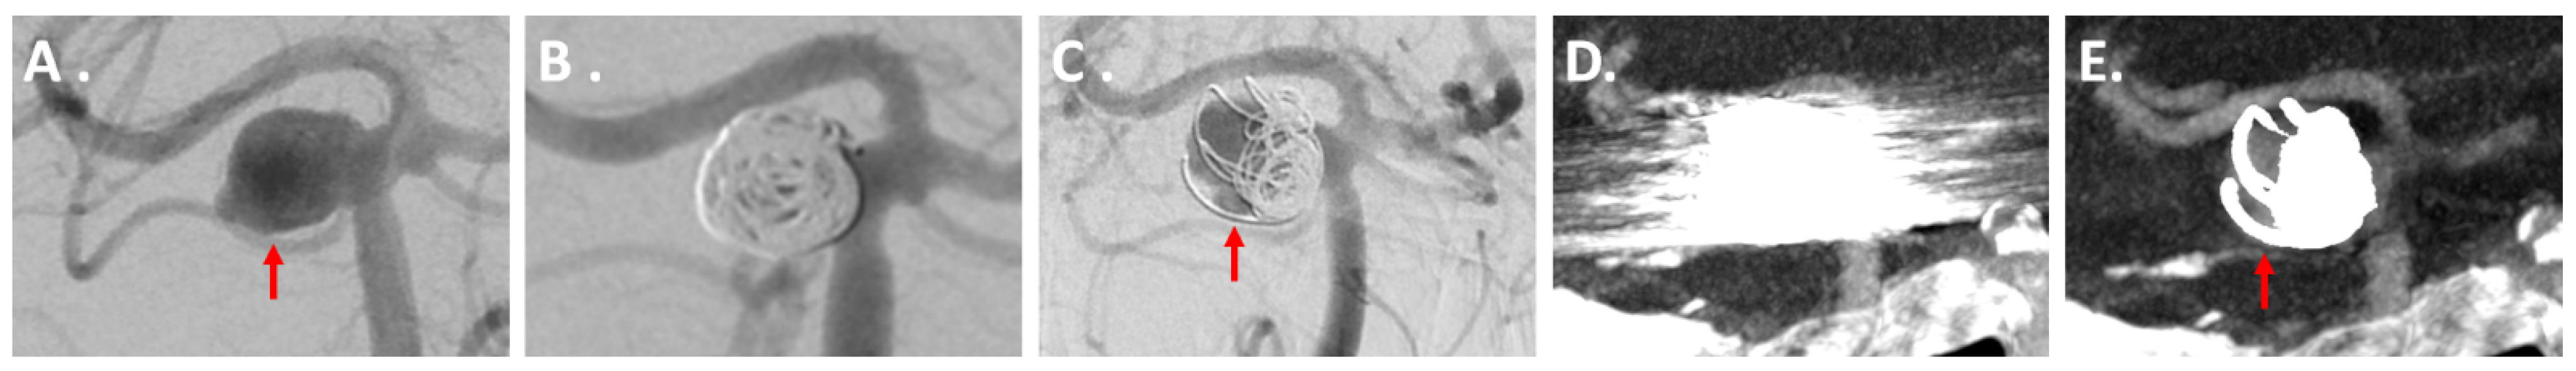

3.3.1. IAs Treated via Coiling